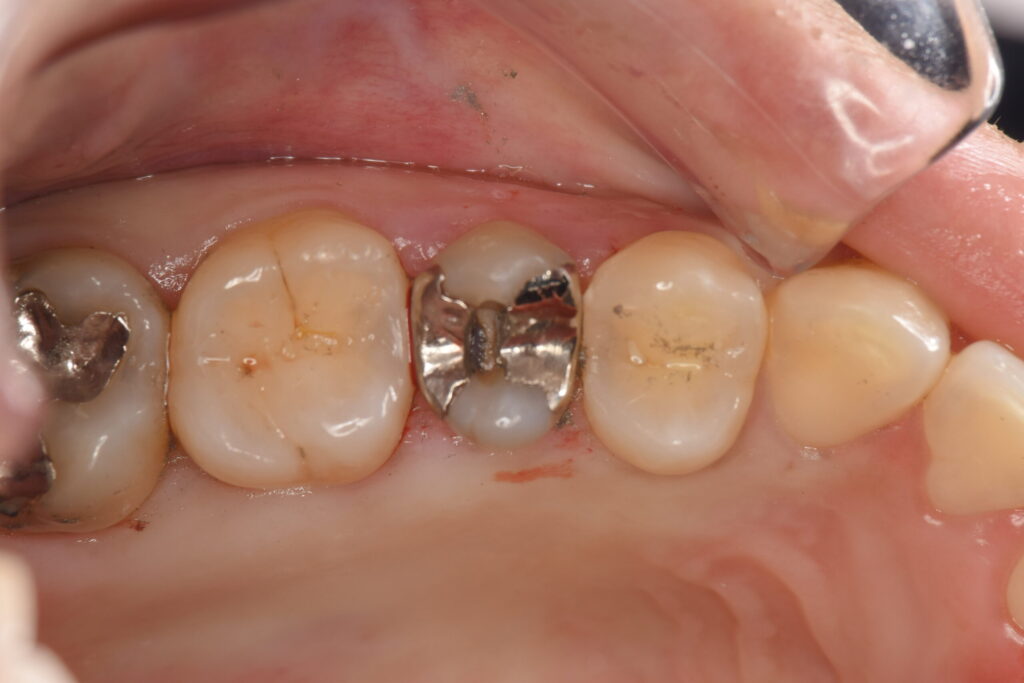

歯にものが挟まるとのことで来院された患者様です。レントゲン検査の結果、銀歯の下に虫歯を認めたため現状と治療法の選択肢、治療法の違いによる予後やメリットデメリットをお話ししたところ、歯髄温存療法(VPT治療)でできるだけ神経治療を回避し、被せ物も再発率が低く見た目が綺麗なジルコニアを希望されました。

銀歯を外してみると、大きく虫歯になっていることがわかります。